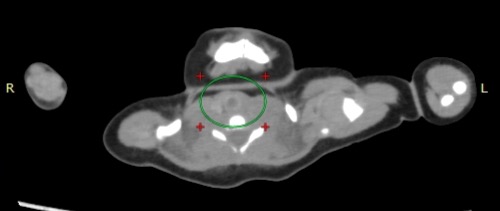

• 肝右葉の下面付近に存在する腸管に径 1~4mm 大の、CT 値が平均で 300 程度の高吸収物が存在する。比較的近い位置に 20 個程度存在する。腸管壁や近接する腸間膜ではなく腸管内腔にあるようにみえるが不明確。周囲の腸管には口径不同などなく通過障害などは発 生していないように見える。

• 腸管内の高吸収物。腸管内の異物、腸溶性の薬剤、壊死性腸炎後の石灰化の可能性など があり得ると思う。SIDS 鑑別の一環として行われるが薬物中毒の検索は行われるべきと思う。